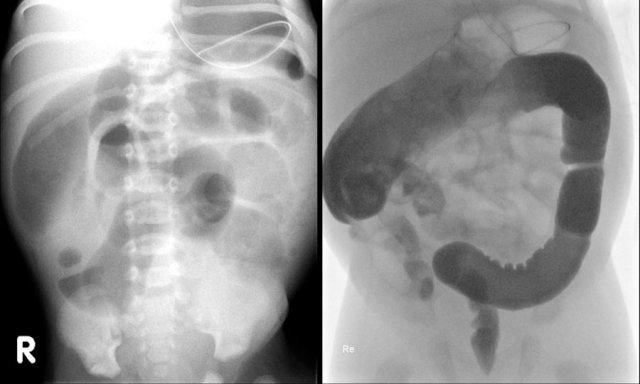

Các dấu hiệu bao gồm:

- Nhiều quai ruột non giãn cho thấy tắc nghẽn đoạn thấp

- Thụt tháo cản quang cho thấy khẩu kính trực tràng nhỏ hơn so với khẩu kính đại tràng sigma

- Trực tràng có hình ảnh co thắt dạng răng cưa.

Chẩn đoán:

Bệnh Hirschsprung đoạn ngắn.